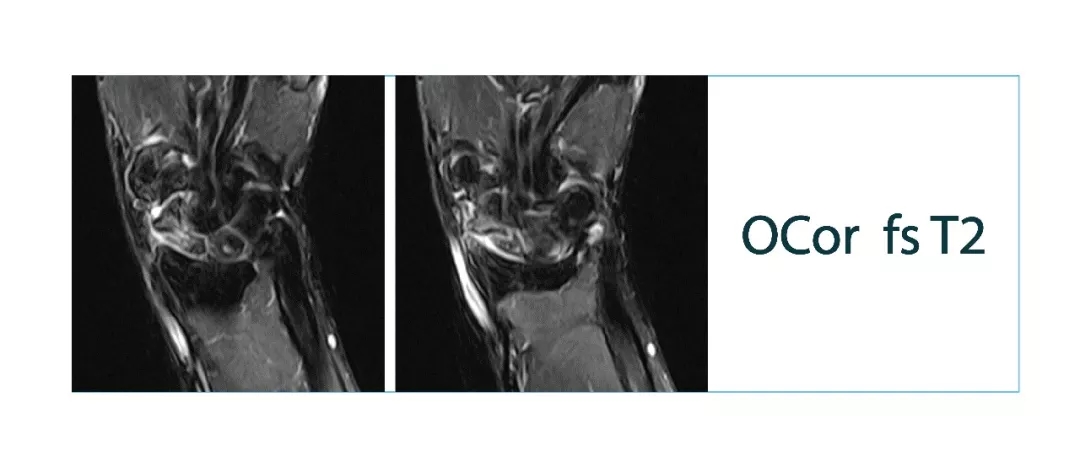

【朗润影像档案】20180126磁共振影像病例结果讨论